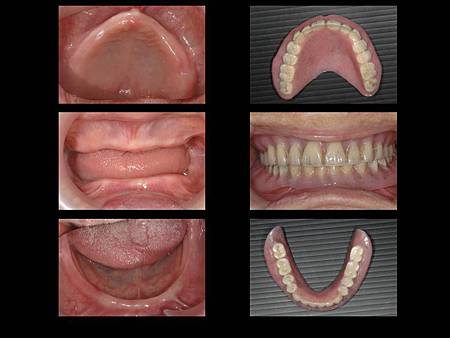

全口無牙的患者, 建議使用人工植牙支撐於假牙下方以增加咬合力

在全口無牙的患者中, 需使用全口活動假牙來恢復咬合功能, 而齒槽脊因時間逐漸萎縮, 活動假牙的固持性會越來越差, 此時可使用人工植牙增加活動假牙下方的支撐, 如此一來假牙較穩固, 患者也才比較可以咬碎食物

患者治療前照相, 隨然佩戴了全口假牙, 但是因為齒槽脊萎縮的關係, 活動假牙不穩定, 患者無法好好的咬碎食物